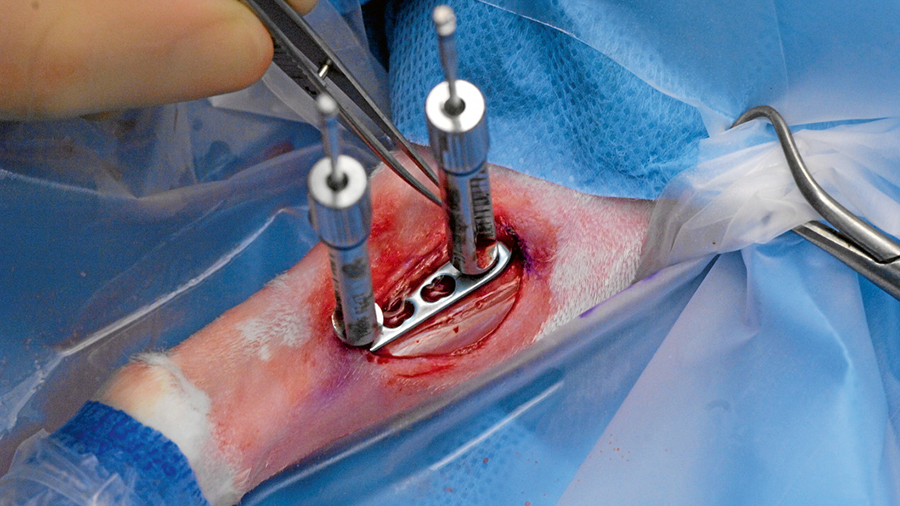

Intraoperative image showing fixation of the humerus with an LCP in our rabbit model of fracture-related infection